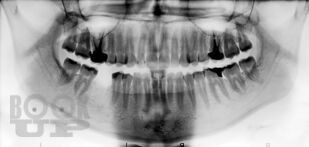

В пособии представлены современные методы ортопедического лечения частичной потери зубов мостовидными протезами. Подробно изложена хирургическая подготовка альвеолярного отростка и альвеолярной части челюстей перед протезированием.